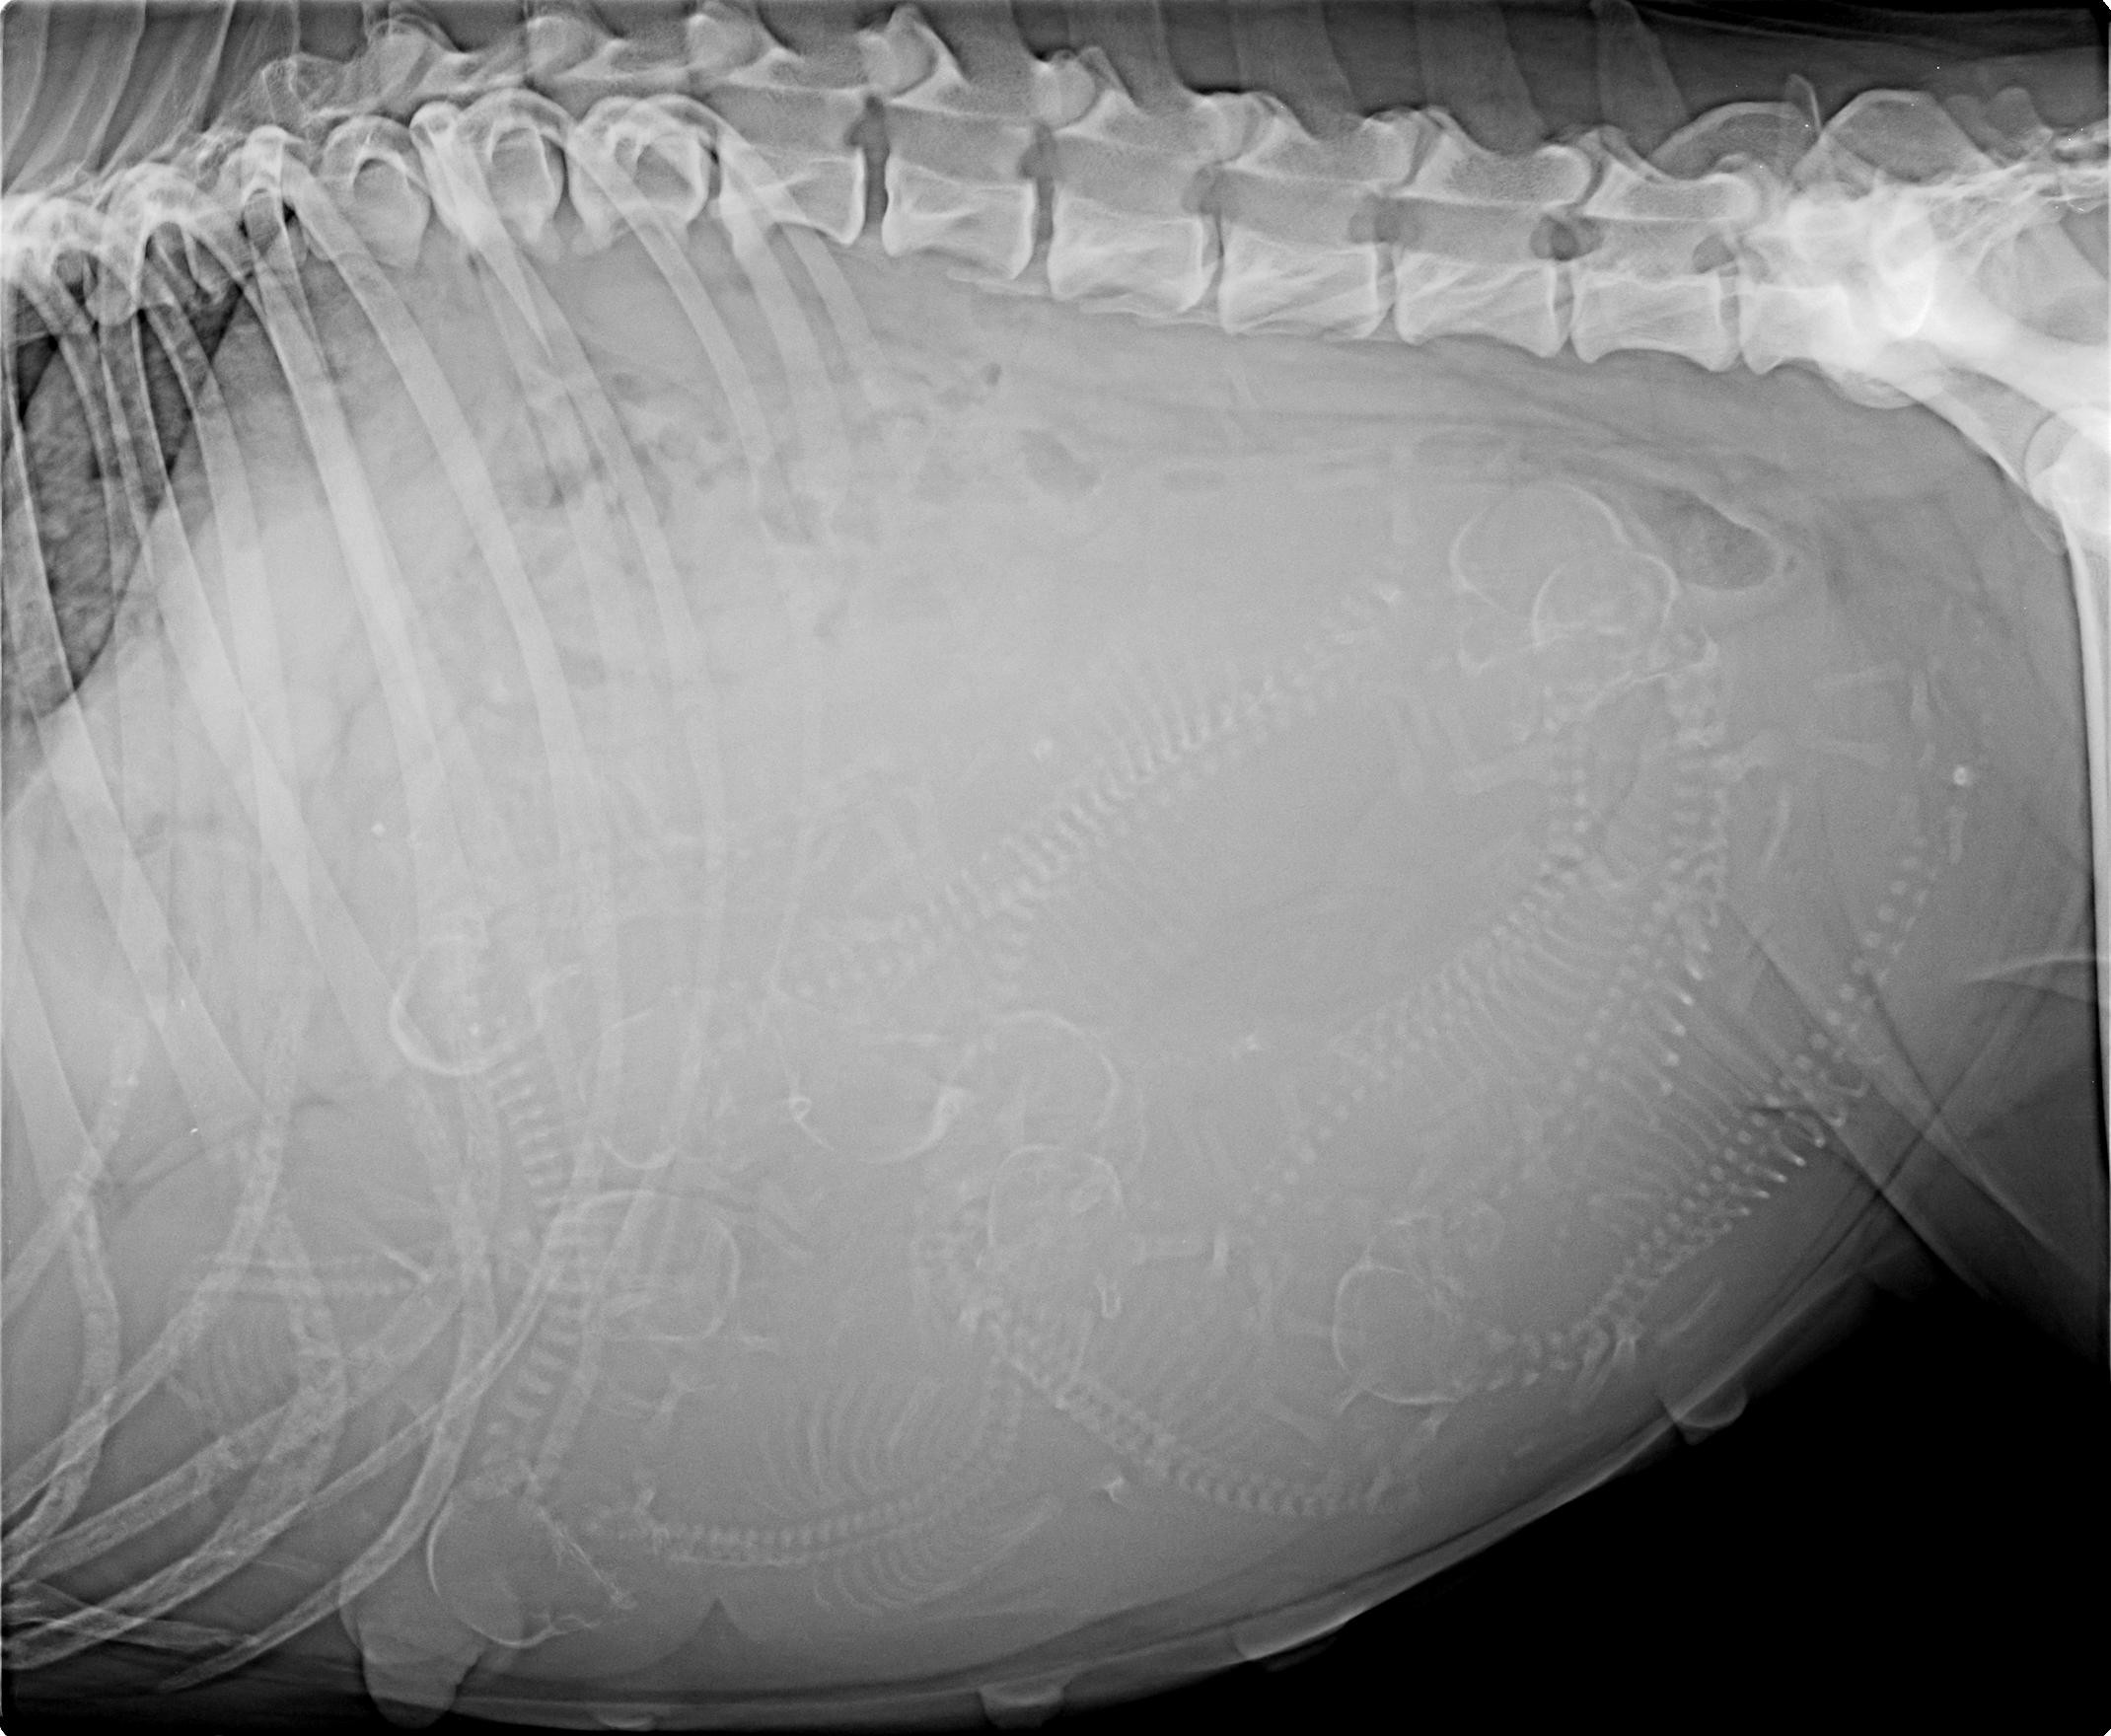

Narození miminek 3.9.2015

Dne 3.9.2015 začala naše Crazynka s tolik očekávaný porodem našich miminek. Bohužel nastali velké komplikace, které byli pro nás až tragické. Takže opožděně sdělujeme, že nám přežilo 5 miminek (3 holčičky a 2 kluci). Crazynka nakonec po císařském řezu je naštěstí již vpořádku.

Porod se blíží 24.8.2015

Dnešní den: pondělí 24.8.2015 (den 53)

Dnes byla naší Crazynce na fakultě v Brně po sonografickém vyšetření potvrzena březost. Předpokládaný termín porodu je cca 4.9.2015